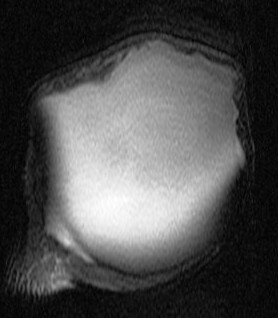

74 y/o female with mass on shoulder. Also pain. Evaluate mass and r/o rotator cuff tear.

Large cyst associated with a rotator cuff tear and AC arthrosis. Geyser phenomenon if communication shown at arthrography (some definitions specify arthrography). This was not an arthrogram. Patient also has a chronic rotator cuff tear. Reference article.

Large cyst above a degenerated acromioclavicular joint ( RID1895 )